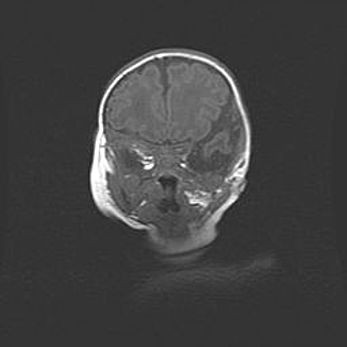

Сообщающаяся гидроцефалия. Кистозная энцефаломаляция головного мозга.

Возраст: 3 месяца 4 дня

Вес: 3100 г

Пол: женский

Окружность головы: 34 см

Срок гестации: 31 неделя

Кистозная энцефаломаляция головного мозга - одна из форм поражения головного мозга в детском возрасте. Характеризуется возникновением множественных и распространённых кист в коре, белом веществе и подкорковых образованиях головного мозга у плодов, новорождённых и детей раннего возраста. Развитие кистозной энцефаломаляции связано с внутриутробной асфиксией и гипотонией, родовой травмой, тромбозом синусов, пороками развития сосудов, инфекциями, сепсисом и другими причинами. Наиболее значимые инфекционные агенты: вирусы простого герпеса, цитомегалии, краснухи, токсоплазмы, энтеробактерии, золотистый стафилококк и другие.